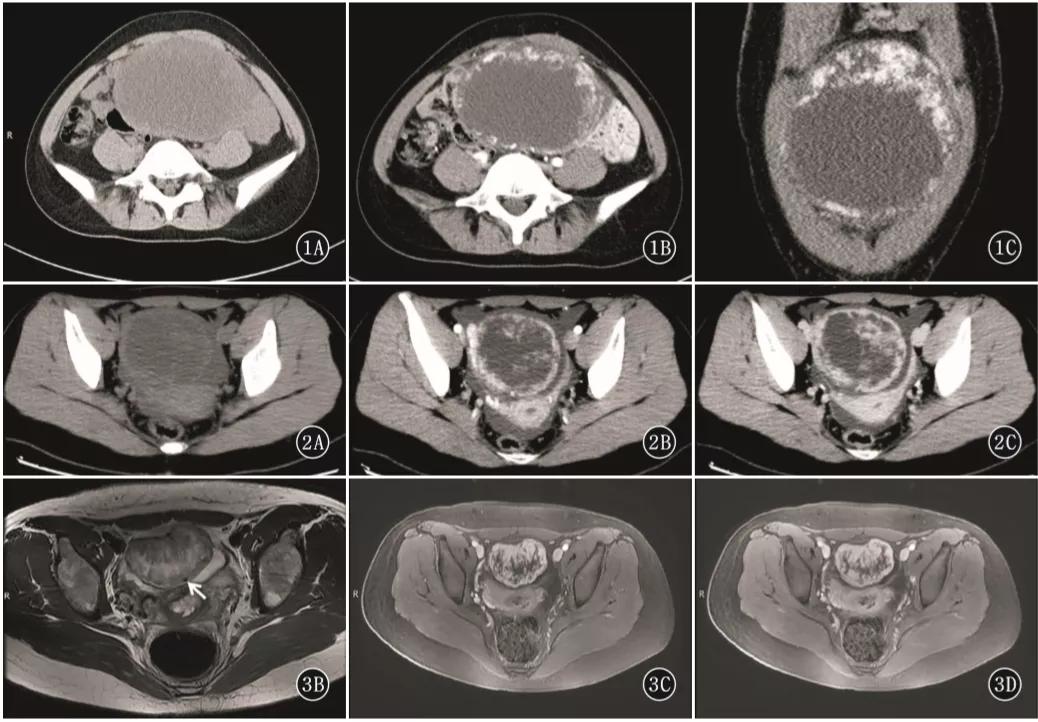

女,47 岁,卵巢子宫内膜样癌。右侧卵巢异常信号肿物,T2WI 混杂稍高及高信号(图 a),DWI 高信号(图 b),增强扫描不均匀强化(图 c)。肿物内见条片状裂隙样异常信号(箭头),T2WI 呈高信号、DWI 低信号、增强扫描未见强化。

女,64 岁,雌激素升高,卵巢子宫内膜样癌。卵巢肿物由三部分构成,偏右侧是囊性成分;中间部分(箭头)T2WI 及 DWI 呈低信号(a 及 b),增强扫描明显强化(c 增强早期,d 增强晚期);偏左侧部分 T2WI 稍高信号,DWI 高信号,增强扫描明显强化。HE 染色显示中间部分肿物由功能性纤维间质构成(图 e)。HE 染色肿瘤左侧部分显示子宫内膜样癌与性索间质肿瘤类似。矢状位显示子宫体积增大(图 g)

女,75 岁,浆液性癌。CA-125 升高。双侧卵巢不规则肿物,与腹膜结节分界不清,T2WI 呈不均匀稍高信号(图 a),DWI 呈不均匀高信号(图 b),CT 显示肿物内钙化(图 c)。箭头显示左侧髂血管旁转移淋巴结。

女,61 岁,雌激素升高。MR 显示左卵巢实性肿物,T2WI 呈稍高信号(图 a),内部多发小囊变(白箭),DWI 呈高信号(图 b),增强扫描明显强化。T2WI 显示子宫腺肌症(箭头)。

女,22 岁,无性细胞瘤。乳酸脱氢酶及碱性磷酸酶升高。T2WI 示右侧卵巢分叶状肿物(图 a),DWI 呈高信号(图 b),增强扫描明显强化(图 c)。箭头显示肿物内可见纤维血管分隔。

女,18 岁,卵黄囊瘤(右侧),AFP 升高。T2WI 示卵巢实性为主肿物(图 a),内见低信号纤维血管分隔(白箭),实性成分 DWI 呈高信号(图 b),增强扫描明显强化(图 c),内见无强化坏死区(箭头)。

女,12 岁,卵巢 Burkitt 淋巴瘤。双侧卵巢肿物,T2WI 信号稍高(图 a),DWI 呈高信号(图 b),增强扫描明显强化(图 c),箭头显示肿物边缘多发囊性结节,为卵泡保留征。

女,34 岁,胃癌双侧卵巢转移瘤。T2WI 显示双侧卵巢实性肿瘤,T2WI 呈高低混杂信号(图 a),DWI 呈高信号(图 b)。